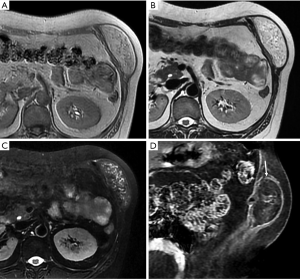

The appearance of abdominal wall endometriosis on CT and MRI depends on the phase of the patient’s menstrual cycle, the chronicity of the process, the number of stromal and glandular elements, and the amounts of bleeding and associated inflammation (63). On CT, anterior abdominal wall endometriosis typically appears as a solid soft tissue mass that is hyperattenuated compared with muscle, although the attenuation can vary and be nonspecific. On MRI, it typically presents as a solid mass that is mildly hyperintense on both T1WI and T2WI as a result of subacute hemorrhage within the endometriotic crypts, although this finding may also vary (Figure 13). Mild to moderate contrast enhancement is present (60).